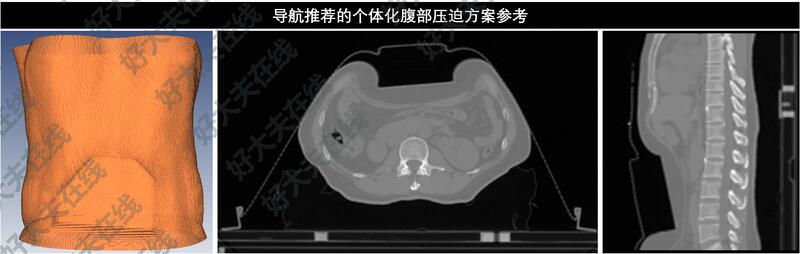

分享一例肝癌寡转移3病灶(肝内2病灶+腹膜后淋巴结)SBRT放疗后长期受控的案例。

51岁浙江女性,2016年因原发性肝癌接受手术切除,病理示:肝细胞性肝癌。后肝内复发,行多周期TACE治疗。

2023年7月外院CT示:肝内多发病灶,右肝后叶占位较前增大;腹膜后淋巴结转移。患者赴我院寻求放疗。

该患者属于肝癌寡转移的情况,给以消融性剂量的放疗(BED>80Gy)有可能获得长期局控甚至治愈。

但患者有3个病灶(肝内2病灶+腹膜后淋巴结),3病灶最大径依次为1.7cm,4.3cm和5.1cm,都不同程度的靠近辐射敏感的胃肠道关键脏器,且患者肝脏术后体积仅1022.6ml。如何至少达到80Gy以上的BED10以获得对病灶的良好局控,同时让肝脏和胃肠道的辐射损伤在可以耐受的范围内,是该患者治疗成功的关键。

对这种疑难的多病灶放疗,经过谨慎的剂量学评估后,最终对3个病灶分别处方SBRT放疗50Gy/8Fx。小肠、结肠和胃均有极小体积的高剂量超标,但在临床可接受范围之内。

患者于2023年8月完成SBRT放疗:50Gy/8Fx(处方BED=81.3Gy,3个PTV内平均BED依次为112.6Gy,107.5Gy,96.4Gy)。